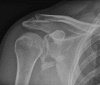

Objectives: This study aimed to evaluate the clinical outcomes of 20 surgically treated patients with displaced glenoid fractures after stabilization with distal radius plate.

Methods: Between 2012 and 2015, at 2 centers (HMCH & SHCE) of Bhubaneswar Odisha, we stabilized 20 scapular intra-articular fractures surgically with distal radius locking plate and studied the outcome of the surgeries. The outcome of the 20 fractures was determined using the Constant and Murley score. Both shoulders were assessed and the score on the injured side was given as a percentage of that on the uninjured side.

Conclusions: Various fixation modalities have been described in the literature, however fixation of intra-articular fracture of glenoid with distal radius locking plate for articular reconstruction in the presented series provides good functional outcome with early restoration of the range of motion of the shoulder.